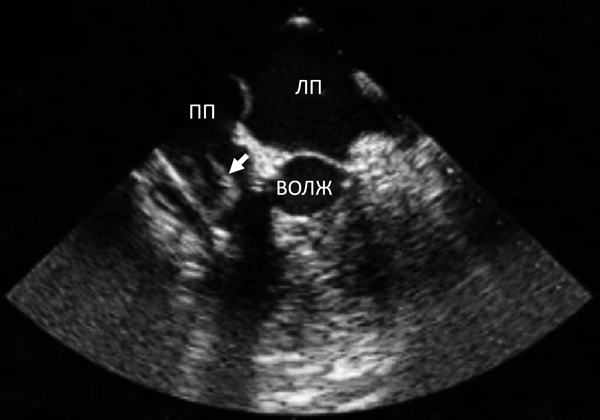

- Прямая визуализация эхопозитивных структур, отходящих от клапана (рис.143).

Бактериальный

эндокардит

трикуспидального

клапана: вегетации,

отчодящие от створок

клапана.